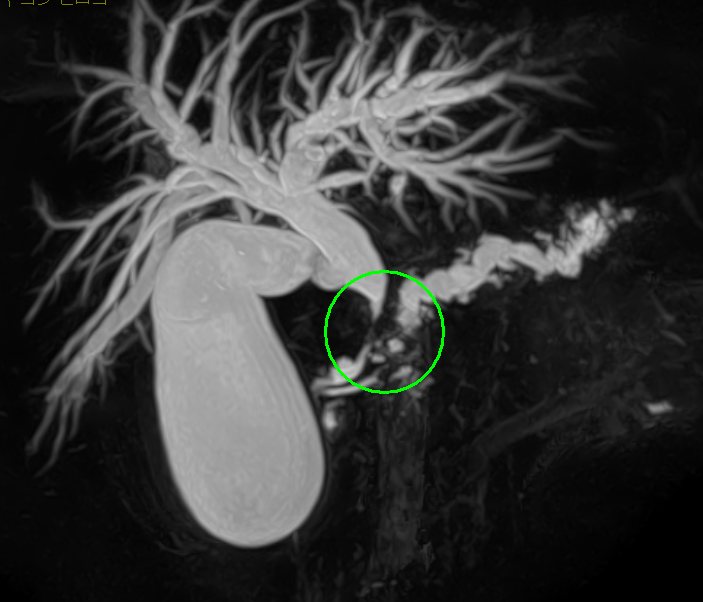

- MRI検査(MRCP)

術前シミュレーション画像(CT画像)

術前の検討